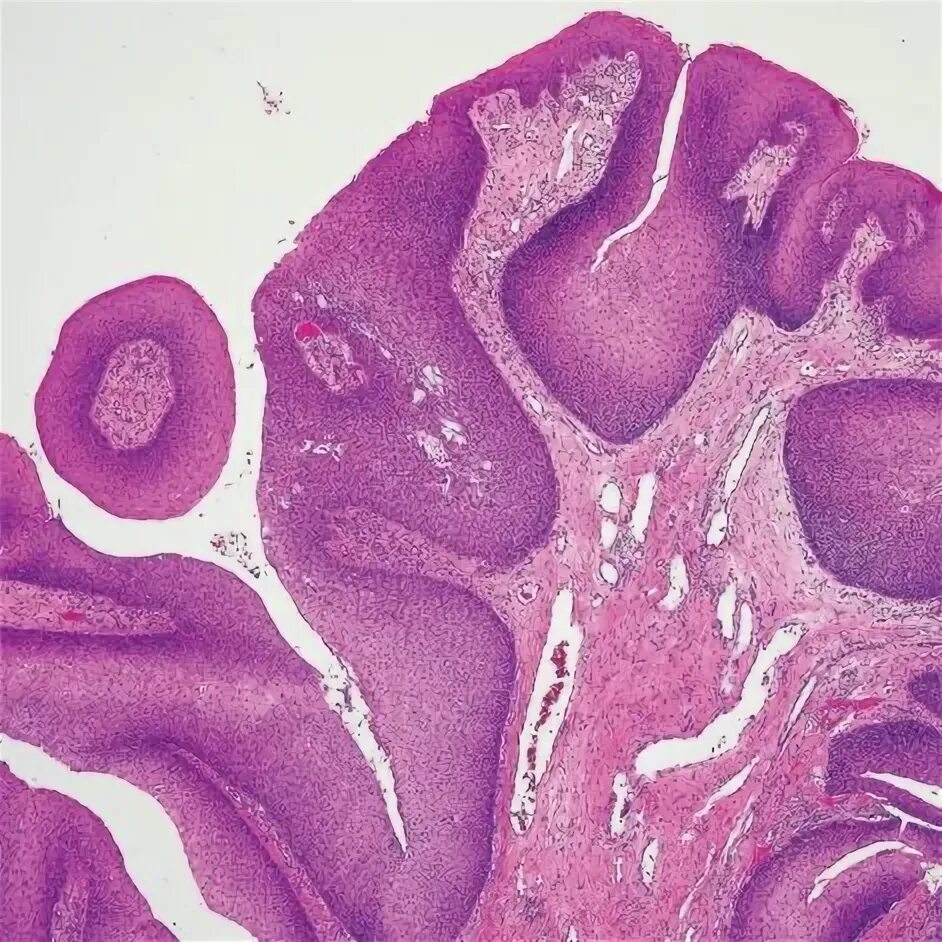

Папиллома гистология